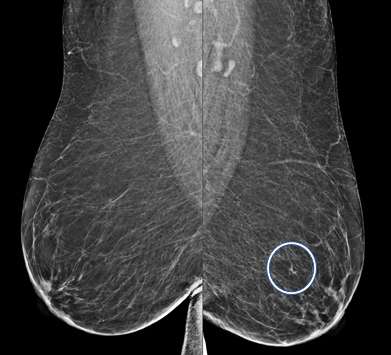

Focal Asymmetry:

A focal asymmetry is a finding seen on two projections3. Focal asymmetries that have been evaluated without suspicious features but persist are likely benign and can be managed with 6-month short-term imaging follow up.

CC views of the breast of the same patient as above demonstrate a correlate to the asymmetry seen on MLO view. This is now a focal asymmetry of the left breast at 3 o’clock.